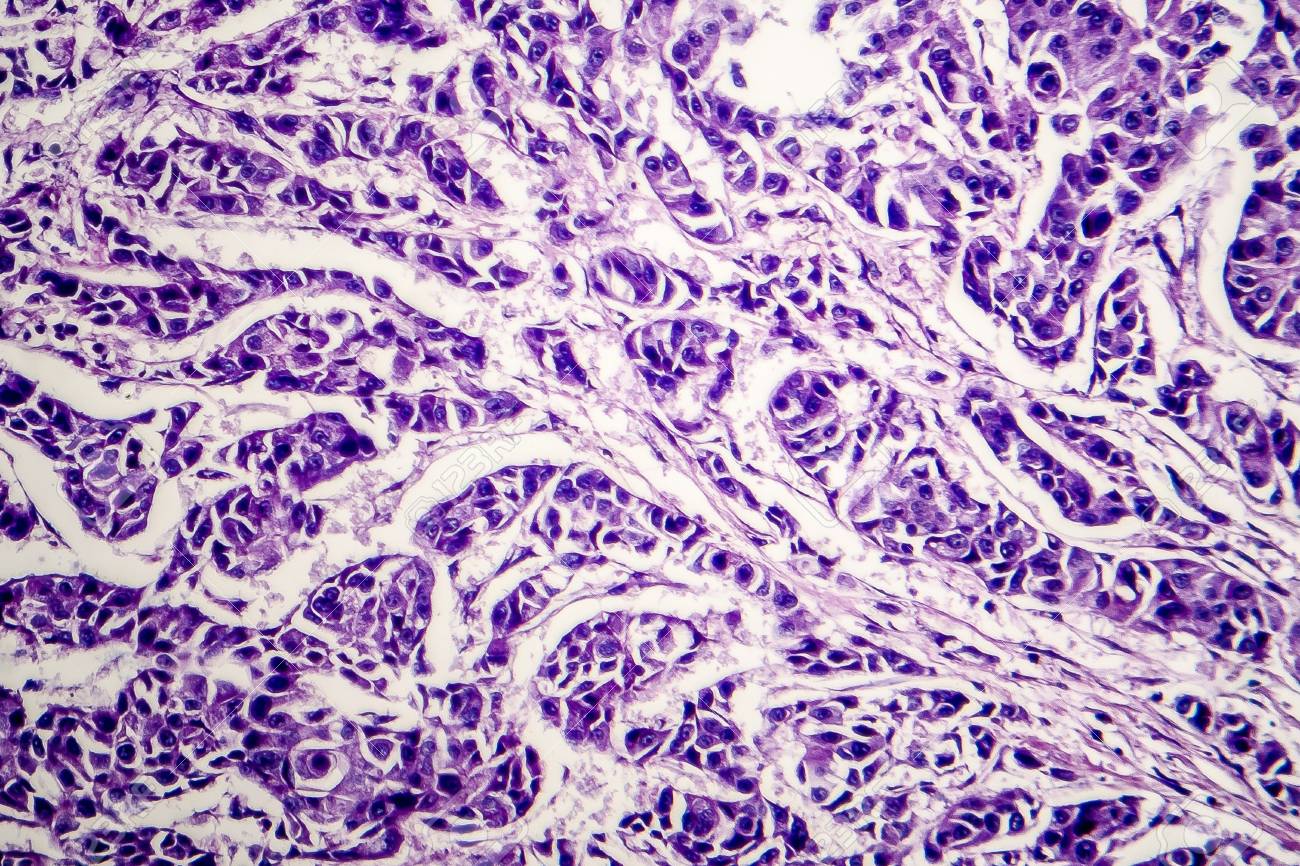

Lymph Node Cancer Light Micrograph Photo Under Microscope

Breast Cancer Lymph Node Metastasis Microscopic Stock Photo

Microscopic View 400x Of The Tumor Located In A Lymph Node